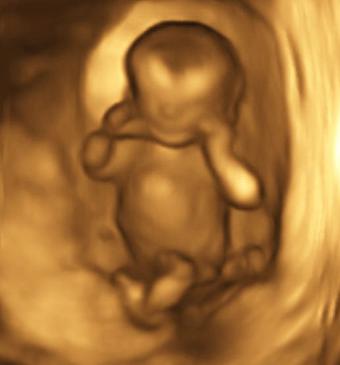

Examinare cu ultrasunete pe trimestrul al doilea (săptămânile 18-21)